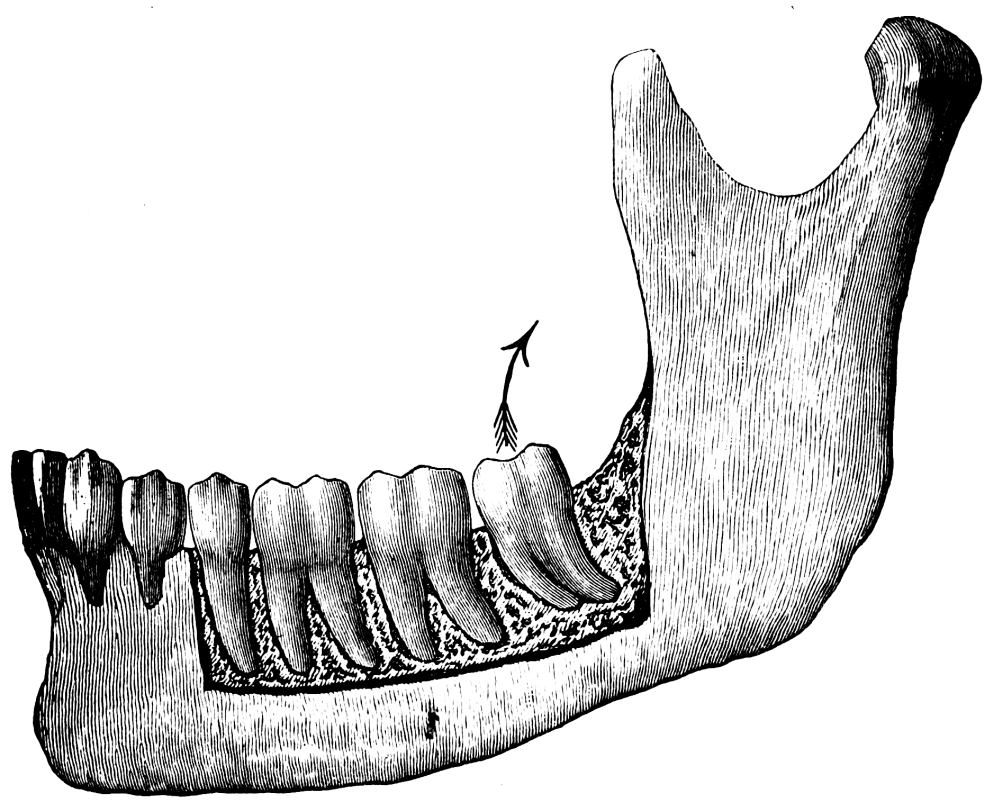

The third molar is best removed with a straight elevator. A glance at the illustration of this tooth (fig. 31) will show that the roots have a well-marked curve backwards, in addition to which the bone forming the socket of this tooth is stronger than is the case with the anterior molars. The removal of the third molar has therefore to be accomplished by using force in a direction upwards and backwards, in other words, in a curve similar to the arc of the circle formed by the roots. This movement cannot well be carried out with forceps, but is easily accomplished with the elevator as follows (it being assumed that the second molar is in place):—Hold the elevator as shown in fig. 13, and insert the blade between the anterior surface of the root and the alveolus, keeping the flattened side of the instrument as far as possible parallel with the root surface. Then force the blade downwards in a direction towards the apex of the root; following this, rotate the handle away from the direction in which the tooth is to{40} be moved. This has the effect of both raising the tooth in its socket and displacing it backward. The edge of the elevator which is to be brought into contact with the surface of the root should be sharp so as to cut somewhat into the cementum. Should this prove insufficient the handle should again be raised and the flattened surface of the instrument brought parallel with the anterior surface of the root and the extractive movement repeated until the tooth is completely raised from its socket.

The value of splitting roots in a case similar to that shown in fig. 33 is apparent, for, as will be seen, it allows each root to be removed in the line of its inclination.

a b

Fig. 33.

(a) Lower molar with divergent roots. (b) The dotted lines show the direction in which the root can be removed if the tooth is divided as suggested in the text.